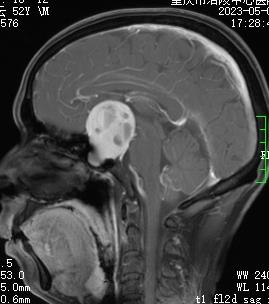

失明不一定是眼睛出问题,有可能是“脑子”的问题

2023-06-02 16:22